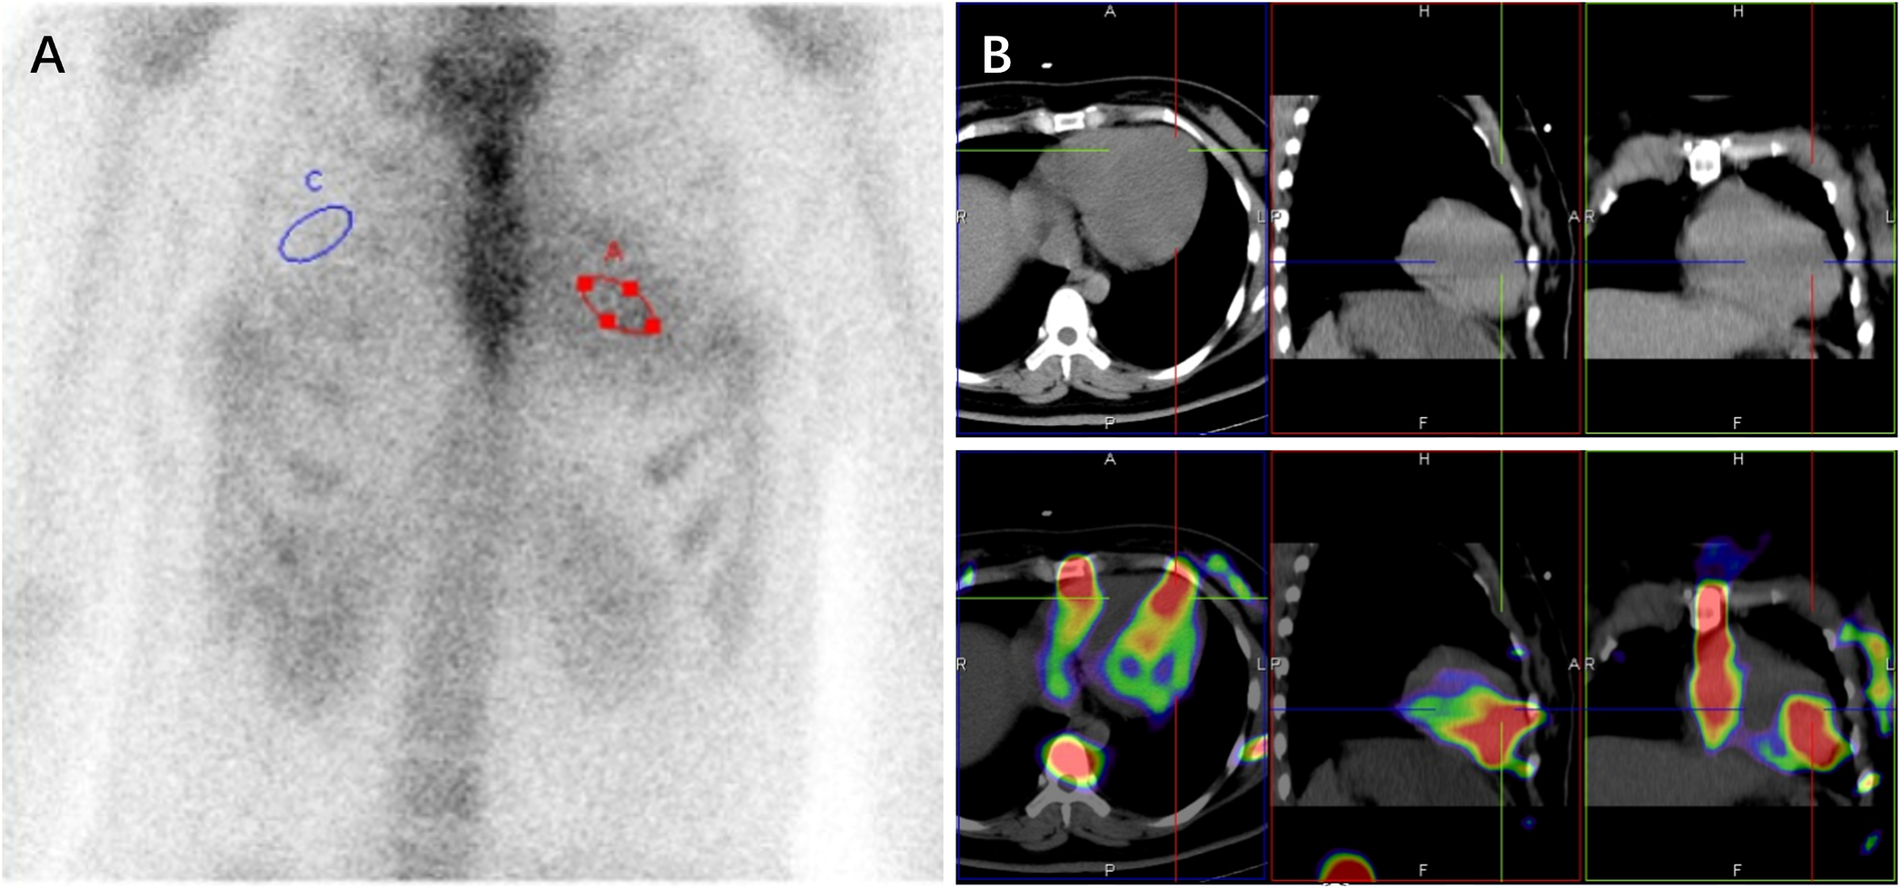

Given the subendocardial LGE pattern on CMR, which raised suspicion for infiltrative disease including cardiac amyloidosis, Technetium-99 m pyrophosphate (99mTc-PYP) scintigraphy was performed, which result demonstrated intense myocardial uptake [visual score Grade 3; heart-to-contralateral lung (H/CL) ratio: 1.82] (Figure 2). With immunofixation electrophoresis (IFE) of serum and urine revealing no presence of immunoglobulin monoclonal proteins, the positive result of 99mTc-PYP scintigraphy seemed to indicate a potential diagnosis of transthyretin amyloid cardiomyopathy (ATTR-CM). Genetic testing detected no pathogenic variant in the TTR gene, effectively excluding hereditary ATTR (ATTRv-CM) and supporting wild-type ATTR (ATTRwt-CM). However, ATTRwt-CM typically affects older individuals, and the clinical presentation was atypical for several reasons: the patient was a young woman of reproductive age, and her EKG lacked low voltage. Furthermore, multiple reports describe false-positive results of 99mTc-PYP scintigraphy in patients with hypertrophic cardiomyopathy (HCM) phenotype (5–11). These discrepancies prompted reconsideration of the diagnosis and led to the recommendation for further genetic testing to evaluate alternative etiologies.

Figure 2

99mTc-PYP scintigraphy (A) and SPECT/CT images (B) revealed a grade 3 myocardial uptake with heart (red circle) to contralateral lung (blue circle) ratio of 1.82 at 3hr (A).